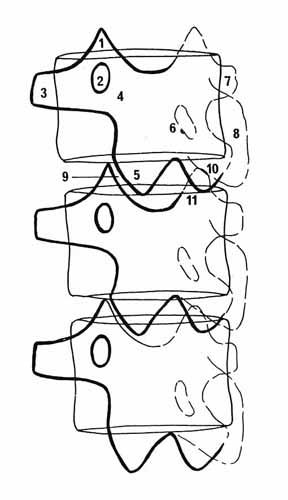

Rachis cervical:  Rachis dorsal: Rachis dorsal:  Rachis lombaire: Rachis lombaire:   1. Processus articulaire supérieur 2. Pédicule droit 3. Processus transverse droit 4. Isthme 5. Processus articulaire inférieur 6. Lame opposée 7. Processus transverse opposé 8. Epineuse 9. Interligne articulaire postérieure 10. Processus articulaire inférieur opposé 11. Processus articulaire supérieur opposé Pour ce qui est de la radioanatomie; nous te laissons le soin d'apprendre tout cela grâce aux livres à ta disposition et à tes stages surtout!  Nous avions commencé une liste de livres de radiologie; à toi de t'en servir et bonnes recherches! Si tu souhaites trouver d'autres correspondances, si quelques détails t'interpellent n'hésite pas à poser des questions précises! Bon courage la marmotte!